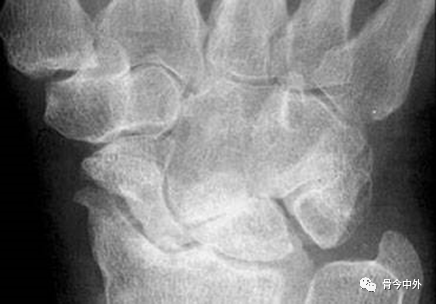

图1 成人期腕关节正侧位及舟骨蝶位片。1.舟骨;2.月骨;3.三角骨;4.豆状骨;5.大多角骨;6.小多角骨;7.头状骨;8.钩骨;9.桡骨茎突;10.尺骨茎突;11.第一掌骨基部。

图2 成人期腕关节正侧位及舟骨蝶位片。1.舟骨;2.月骨;3.三角骨;4.豆状骨;5.大多角骨;6.小多角骨;7.头状骨;8.钩骨;9.桡骨茎突;10.尺骨茎突;11.第一掌骨基部。

图3 成人期腕关节正侧位及舟骨蝶位片。12.舟骨结节。黑色箭头:舟骨腰部;白色箭头:舟骨滋养血管影。